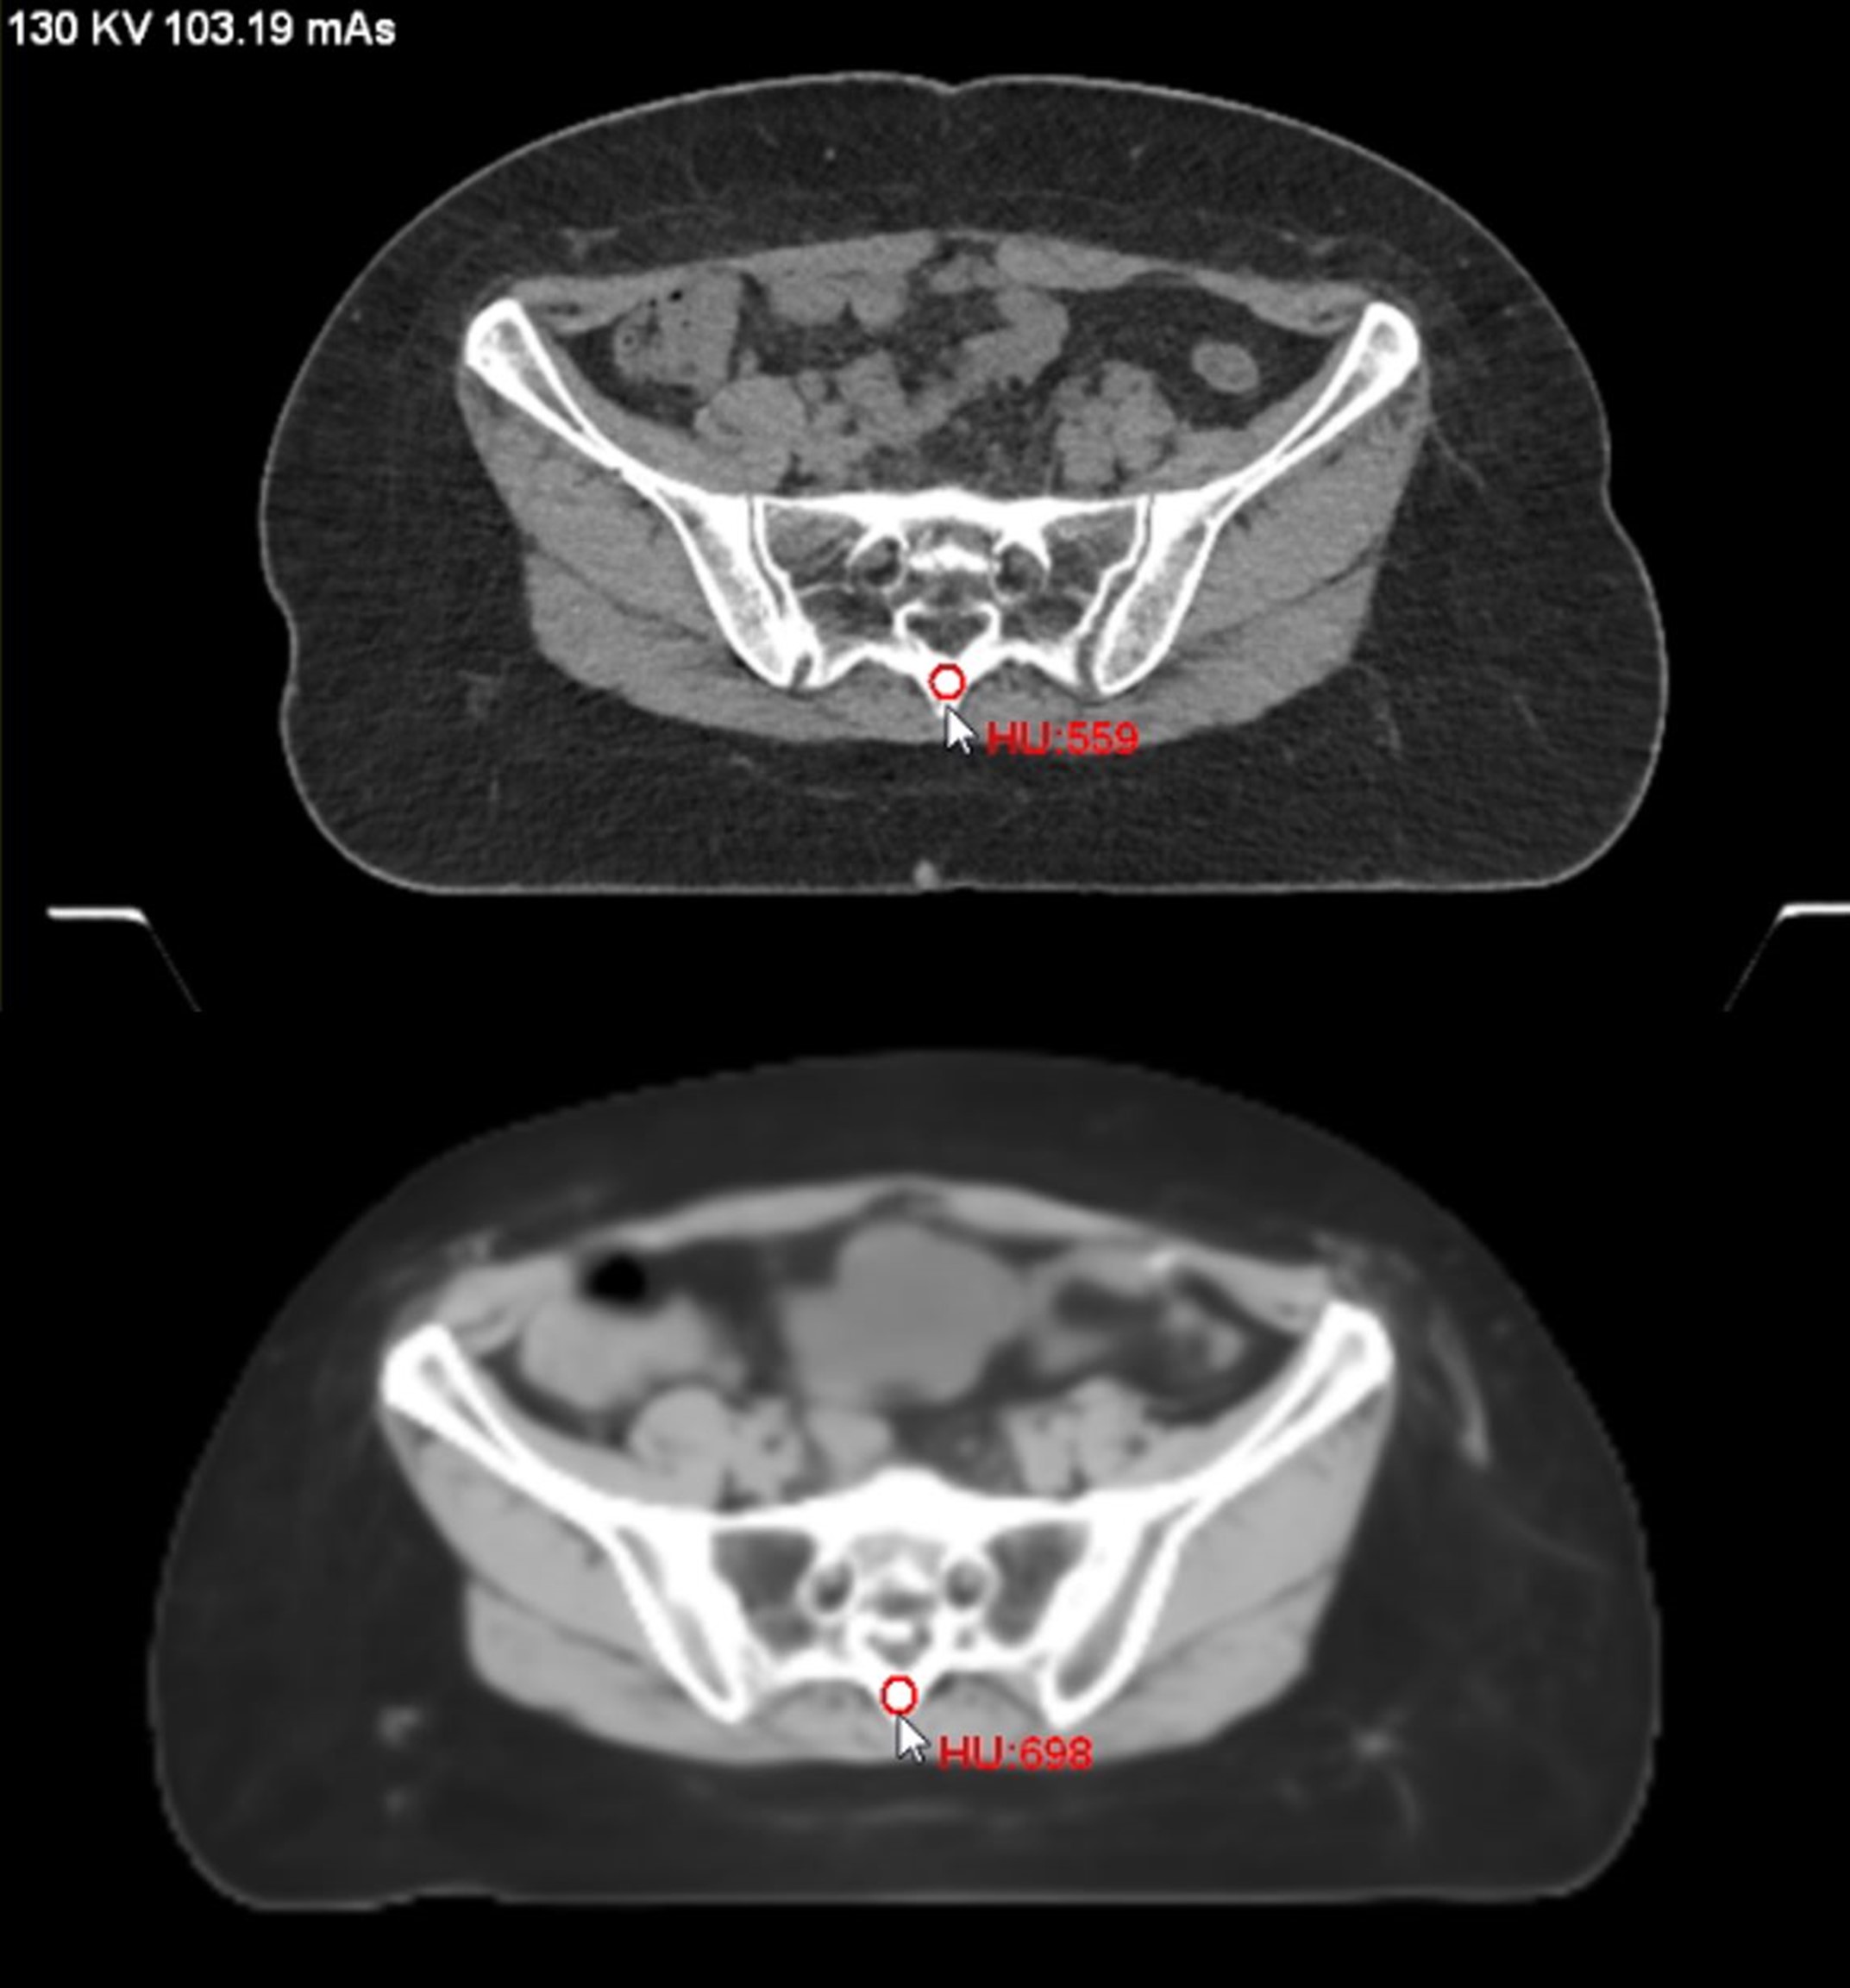

Metodele precedente de obținere a datelor echivalente CT din RM implicau una dintre următoarele trei metode sau o combinație a acestora. Prima presupunea clasificarea fragmentelor de imagine IRM (voxeli) ca fiind aer, grăsime, țesut moale sau os și atribuind apoi coduri diferite pentru fiecare tip de țesut. A doua abordare a implicat un model bazat pe învățare. O funcție de „cartografiere” asocia intensitățile voxelilor RM cu unitățile Hounsfield corespunzătoare pe CT.

Noua abordare (care implică rețele convoluționale de deep learning) permite obținerea unui rezultat de calitate folosind o singură secvență IRM. Cu excepția stratului de intrare și a stratului de ieșire, există și alte straturi ascunse care procesează informațiile prin aplicarea mai multor filtre. Fiecare strat primește, procesează și transmite informații celui următor. În acest fel, sunt recunoscute caracteristici de complexitate crescută, rafinând rezultatul.

Pentru a îmbunătăți performanța unor astfel de modele, a fost creat un alt tip de rețea. Rețelele adversariale generative (GAN) au rezultate impresionante în generarea de imagini și translatarea imagine-la-imagine (6). Aceste structuri reunesc cel puțin o rețea care generează imaginile și una care le verifică – discriminatorul (7). Discriminatorul compară sCT cu scanări CT reale și respinge ca „false” imaginile pe care le cataloghează ca nefiind un CT real. În acest fel, generatorul învață să producă „falsuri” mai bune, până când devine atât de priceput, încât poate înșela discriminatorul crezând că CT-urile false ar fi CT-uri reale.